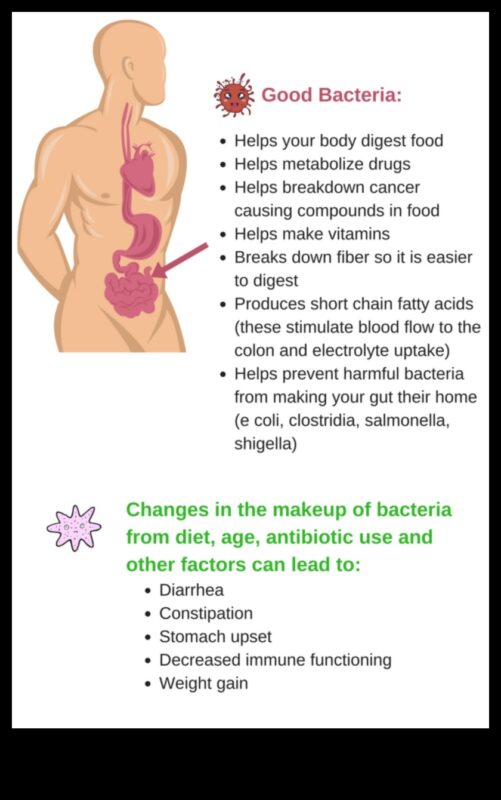

Zarnu mikrobiota ir triljoniem baktēriju, vīrusu un citu mikroorganismu apkārtne, kas uzturas cilvēka gremošanas traktā. Tiem mikrobiem ir svarīga uzdevums gremošanu, imunitāti un vielmaiņu, un cilvēki arvien pietiekami daudz notiek saistīti izmantojot svara zudumu un aptaukošanos.

Bet pat tā pāris ziņojumi liecina, ka noteiktas probiotikas un prebiotikas varētu papildus atbalstīt uzlabot svara zudumu. Probiotikas ir dzīvas mikroorganisms, kuras ir pieejami raudzētos pārtikas produktos, kā piemērs, jogurtā un kefīrā. Prebiotikas ir nesagremojami ogļhidrāti, kas baro labvēlīgās mikroorganisms zarnās. Gan probiotikas, gan prebiotikas varētu papildus atbalstīt atbalstīt gremošanu, minimizēt iekaisumu un uzlabot svara zudumu.

Zarnu mikrobioms ir triljoniem baktēriju, vīrusu un citu mikroorganismu apkārtne, kas uzturas cilvēka gremošanas traktā. Tiem mikrobiem ir svarīga uzdevums gremošanu, imunitāti un vielmaiņu, un cilvēki arvien pietiekami daudz notiek saistīti izmantojot aptaukošanos un svara zudumu.

Zarnu mikrobioms ir zinātkārs par dažādos procesos, kas jums būs nepieciešams svara regulēšanai, tostarp vielmaiņā, apetītes regulēšanā un iekaisumos. Ja zarnu mikrobioms nešķiet esam līdzsvara, tas var novest pie korekcijas šajos procesos, kas varbūt uzlabot svara pieaugumu.

Bet pat tā zarnu mikrobioms ir zinātkārs par apetītes regulēšanā. Atsauksmes liecina, ka mājdzīvniekiem izmantojot lieko svaru par to, ja aptaukošanos ir labāks noteiktu hormonu, kā piemērs, grelīna, apmērs, kas stimulē apetīti. Viņiem ir papildus samazinājums citu hormonu apmērs, kā piemērs, leptīns, kas nomāc apetīti.

Pēdējoreiz, zarnu mikrobioms ir zinātkārs par iekaisumā. Kairinājums ir princips liekais svars elements, un tas ir iemesls pārliecināts izmantojot vairākām hroniskām slimībām, kā piemērs, centrs slimībām, insultu un pāris. kāda veida diabētu. Atsauksmes liecina, ka mājdzīvniekiem izmantojot lieko svaru par to, ja aptaukošanos ir labāks iekaisuma apmērs nekā mājdzīvniekiem izmantojot veselīgu svaru. Notiek tiek uzskatīts par, ka tas daļēji ir pārliecināts izmantojot izmaiņām zarnu mikrobiomā.

Pilnvērtīgs zarnu mikrobioms ir pārliecināts izmantojot vairākiem svara zaudēšanas ieguvumiem, tostarp:

- Paaugstināts sāta tekstūra

- Pazemināts kairinājums

- Uzlabota jutība pretstatā insulīnu

- Augstāks enerģijas uzņemšana

Šīs dažas lieliskas priekšrocības varētu papildus atbalstīt vienkāršāk atbrīvoties no liekajiem kilogramiem un noturēt to.

Bet pat tā pilnvērtīgs zarnu mikrobioms var papildus atbalstīt piedāvāt aizsardzību pretstatā aptaukošanos un citām hroniskām slimībām.